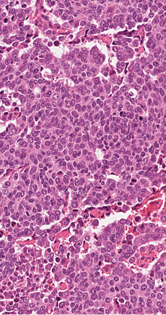

2 pav. Trys naviko komponentai: solidiniai epiteioidinių ląstelių lizdai, kuriems būdingos pavienės spindžius primenančios struktūros (A), pluoštais besidėstančios šeivinės ląstelės (B) ir diskohezyvios „rabdoidinės“ ląstelės, turinčios ekscentrišką citoplazmą (C)

Mikroskopiniuose preparatuose (1 pav.) matyti infiltratyviai žarnoje plintantis navikas, sudarytas iš trabekulinų, lizdinių ir solidinių struktūrų su pavieniais likutiniais spindžiais, kurias formuoja mišri ląstelių populiacija (2 pav.): dominuoja epitelioidinės kohezyvios ląstelės (apie 40 proc. naviko), pasižyminčios negausia ir vidutinio gausumo eozinofiliška citoplazma, smulkaus ir stambesnio kalibro centruotais, ovaliais arba nelygaus kontūro, polimorfiškais branduoliais. Šeivinės ląstelės sudaro apie 30 proc. naviko, ląstelių citoplazma vidutinio gausumo, eozinofiliška, ląstelėse ištęsti vidutinio kalibro branduoliai. Likusią dalį (apie 30 proc. naviko) sudaro diskohezyvios rabdoidinės išvaizdos ląstelės periferizuotais branduoliais ir ryškiomis nukleolėmis, ekscentriška citoplazma ir eozinofiliniais intracitoplazminiais inkliuzais. Matyti gausios mitozės (40/2 mm2), nekrozės iki 10 proc. naviko tūrio, granuliacinis audinys išopėjusiame paviršiuje. Identifikuotas perineurinis naviko plitimas ir intravaskulinė (smulkių šakų ir intraveninė) invazija; naviko struktūros siekė cirkuliarų rezekcijos kraštą. Antrąjį židinį formavo analogiškos to paties naviko struktūros su negausiu likutiniu limfoidiniu audiniu periferijoje (tikėtina metastazė pasaito limfmazgyje, ekstranodaliai plintanti į žarnos sieną).